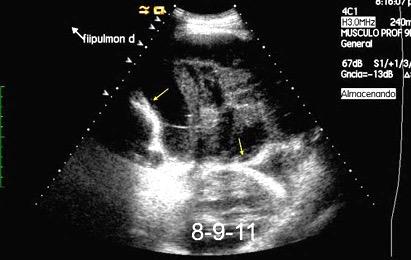

Patrón ecográfico de empiema

Anecoico.....0%. (0 de 47)

Complejo no septado no hiperecoico... ……………..0% (0 de 36)

Complejo, no septado hiperecoico......100% (2/2)

Complejo septado …35% (11 de 31)

Ecogénico homogéneo .... 100% (2 de 2)

Wang T et al. Value of ultrasonography in determining the nature of pleural effusion. Analysis of 582 cases. Medicine 2022.

Chih-Yen Tu et al. Chest Ultrasound Study Pleural Effusions in Febrile Medical ICU. Chest 2004